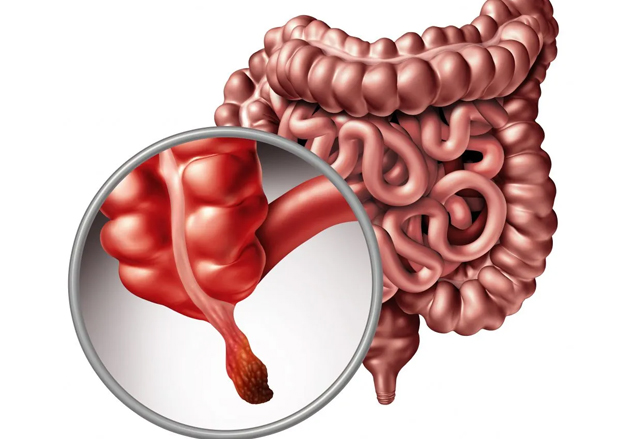

A apendicite é uma inflamação do apêndice cecal, um órgão tubular fino em forma de dedo que se projeta do cólon, no lado inferior direito do abdômen.

A causa mais provável da apendicite é uma obstrução no interior do apêndice, que resulta em infecção.

As bactérias se multiplicam rapidamente, fazendo com que o apêndice fique inflamado, inchado e cheio de pus.

Se não for tratado, o apêndice pode se romper.